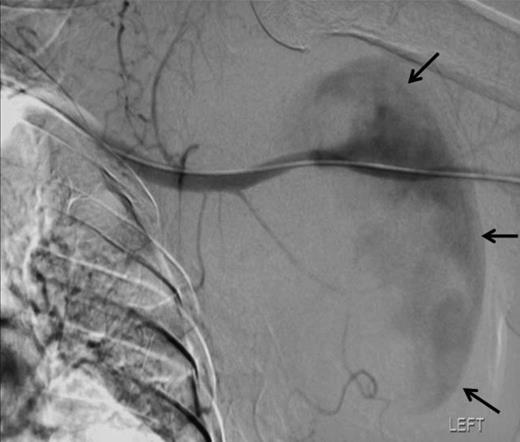

Angiographic localisation of the lesion in the third part of the axillary artery. Please note extravasation of contrast into the sac (arrows)

Pseudoaneurysms after blunt trauma to the shoulder tend to occur in the third part of the axillary artery (7). One theory for this is the lesser mobility of this region of artery because of the relatively fixed nature of the circumflex humeral and subscapular arteries, leading to tearing of the axillary artery with attempts at mobilisation (3,4). There are at least 27 reported cases in the literature of axillary pseudoaneurysm as a complication of anterior shoulder dislocation. We are unable to find any cases reported in the absence of a bony injury in blunt trauma.

The lesion was repaired by an endovascular retrograde approach whereby the neck of the lesion was located just distal to the origin of the subscapular artery and the cavity excluded successfully by the insertion of self-expanding Fluency nitinol PTFE-covered stent (Bard). Such a method was favoured here because the condition of the arm rendered open approaches hazardous. There are several reports of the treatment of such lesions by stent graft, including those of Xenos (10), whilst open repair also offers a simultaneous opportunity to explore for and deal with associated injuries.